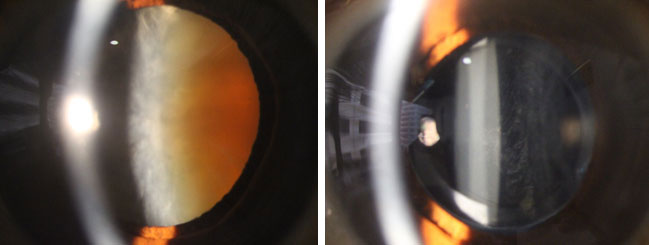

白內障手術前(左圖) 和後 (右圖)

眼科專科鄧維達醫生表示,現今的白內障手術,傷口較以往的手術大大縮小,以微創手術方式使用超聲波乳化技術,將混濁的晶體清除,再經由可捲曲的人工晶片植入眼內,手術便告完成。手術一般10至15分鐘左右,大部份可於表層局部麻醉(topical anaesthesia) 的方式進行,大多不需縫針或進行注射,讓手術過程更舒適快捷。